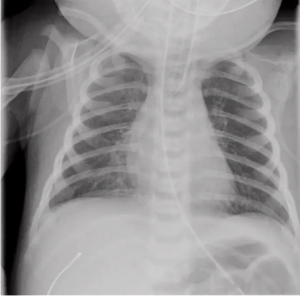

Для подтверждения диагноза необходимо наличие рентгенологических изменений (УЗ или КТ-признаки) и/или наличие клинических и лабораторных данных (таблица 1 и 2).

Основной критерий диагностики врожденной пневмонии:

Наличие инфильтративных или очаговых теней на рентгенограмме легких.

Комментарии: Рентгенологические симптомы врожденной пневмонии не обладают необходимой специфичностью и достаточно вариабельны, поэтому только на их основании затруднительно сделать заключение об этиологическом факторе воспалительного процесса. Возможно двустороннее поражение легочной ткани, как правило, в виде неоднородной картины легких — сочетание участков уплотнения легочной ткани и компенсаторного повышения воздушности, возможен выпот в плевральных полостях [17,18].

Неоднородные изменения легочного рисунка в сочетании с плевральным выпотом позволяет с большой вероятностью предположить наличие врожденной пневмонии, в первую очередь, вызванной стрептококком группы В [17,19]. Возможно наличие очагов уплотнения легочной ткани. Выраженное уплотнение, ограниченное одной, отдельно взятой долей, сравнительно редко встречается у новорожденных [20]. Врожденная пневмония должна исключаться при появлении новых инфильтративных затенений или при сохранении рентгенологических изменений в течение 48 ч после рождения.

Рентгенологически отличить респираторный дистресс синдром и врожденную пневмонию у недоношенных новорожденных в первые 72 часа затруднительно, в этой связи возможными рентгенологическими признаками, свидетельствующими в пользу врожденной пневмонии у недоношенных детей, по сравнению с РДС, могут быть появление крупно- и мелкоочаговых теней на фоне грубой сетчатости легочного рисунка, сгущение легочного рисунка в прикорневых зонах, значение кардио-торакального индекса менее 0,5 в возрасте 72 ч жизни [3].